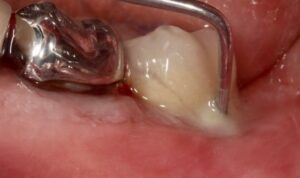

Au stade de « péri-implantite » il s’agit d’une atteinte inflammatoire des tissus mous entourant un implant. Le diagnostic clinique comprend un saignement au sondage, avec une suppuration quasi systématique, et une profondeur de poche péri-implantaire supérieure ou égale à 5 mm. Radiographiquement, un aspect radioclair de déminéralisation osseuse marginale supérieure ou égale à 2 mm entoure une partie plus ou moins étendue du corps de l’implant (fig 1 et 2).

Figure 2: aspect radiographique de la perte osseuse confirmant la péri-implantite